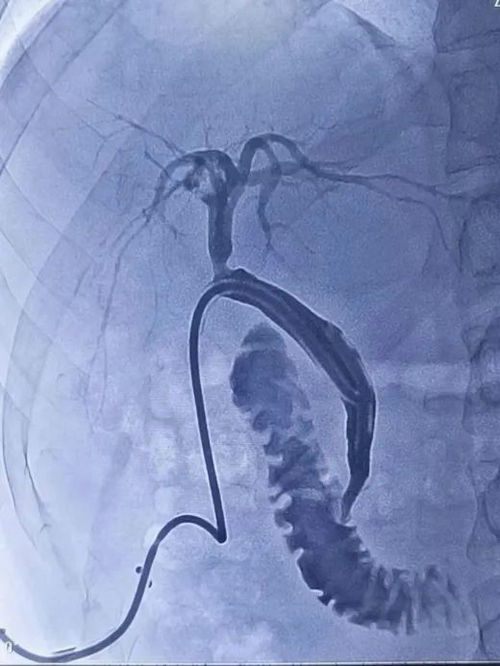

后经T管造影发现肝内胆管多发血栓形成

通过反复抽吸冲洗抽出大量血栓

吕军主任为其留置微导管后进行胆管内溶栓治疗

▲ 造影提示胆管内大量血栓

▲ 冲洗后的胆道造影图像

▲ 术后造影复查图像

术后三天经T管复查造影,可见肝内胆管血栓影明显减少,远端胆管显影,胆管未见明显扩张,毛先生对治疗效果十分满意!